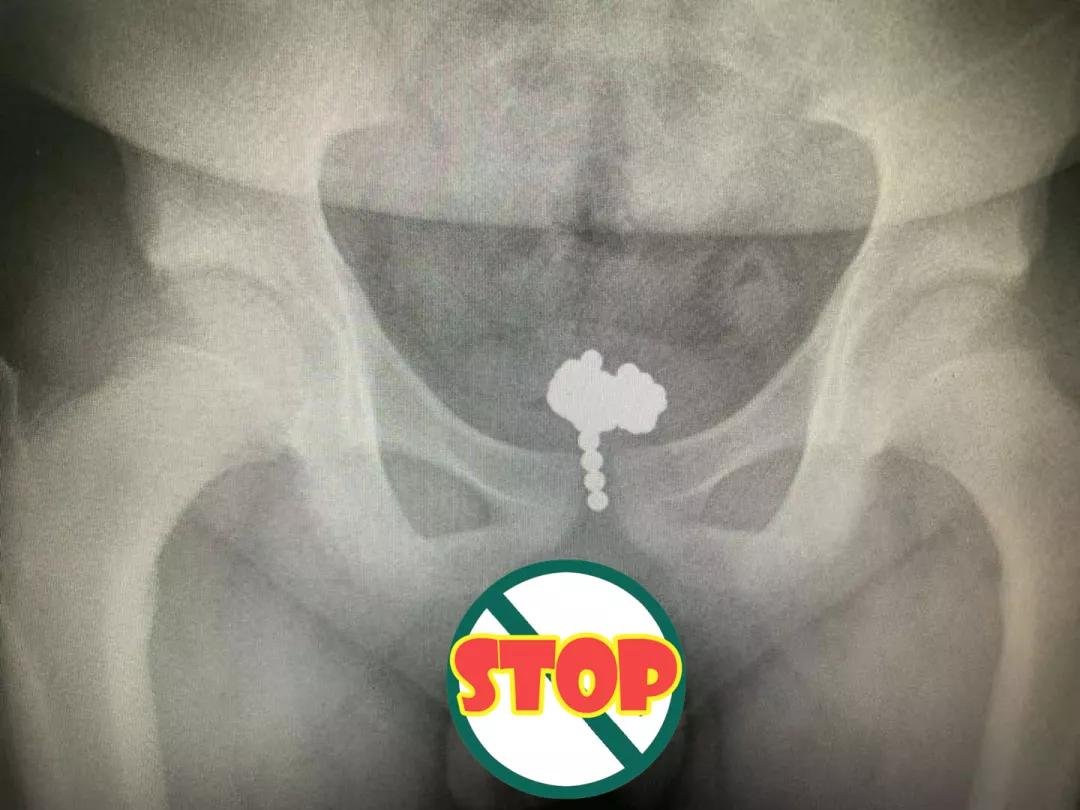

磁力珠

这可以说是外科医生最讨厌的玩具了小朋友们是真的“勇”

嘴巴、耳朵、尿道、阴道……

只要你有孔 我就敢往里塞

11岁男孩把70颗磁力珠塞进尿道3个孩子误吞磁力珠引发肠穿孔,做了开腹手术

2岁男童一次性吞15颗磁力珠,嵌入了体内组织

……

在临床中碰到太多误食磁力珠导致肠穿孔的病例了

一年至少能遇到十多例

对待磁力珠,一定要谨慎、谨慎、再谨慎